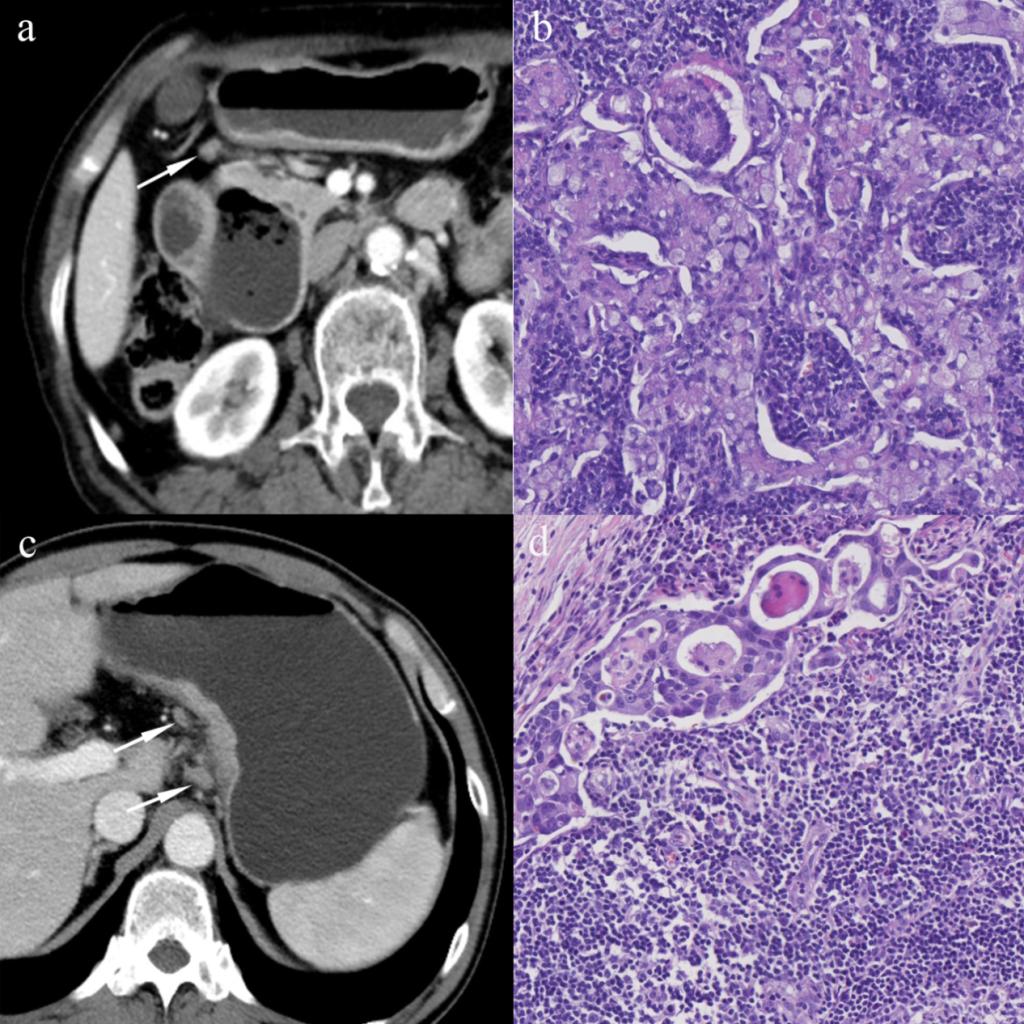

图1 区域淋巴结的CT及病理影像